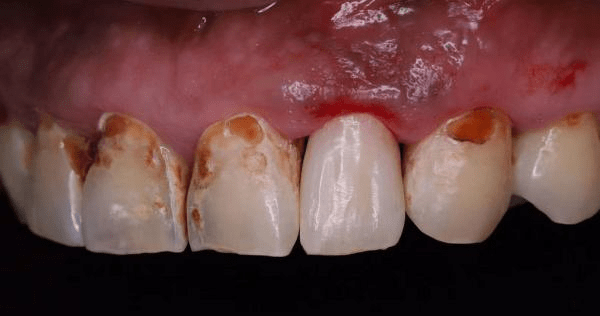

“门诊又见‘可乐牙’,这小哥哥管不住自己的嘴,这一口牙可是惨了!”近日,宁波牙科医生穆锦全在朋友圈里分享了两张牙齿的照片。

照片上的满口牙,几乎每一个上面都有大小不等的缺损,呈现发黑或发黄的颜色,有的牙齿上还有白点。

穆锦全医生分享的照片,来自一位20岁的小伙子。穆医生告诉记者,这位小伙子来医院不是来看牙的,而是希望来给牙齿做矫正的,但医生打开他的口腔,发现几乎每一个牙齿上面都有大小不等的缺损。

“这个小伙子就是典型的‘可乐牙’,这么严重的情况在门诊并不多见。”穆锦全医生说,这位小伙子的牙齿已经非常脆弱,根本没法矫正,牙齿表面的黑斑和黄斑如果用探针往下探,很容易触及牙齿的本质,牙齿马上就会感觉痛了。